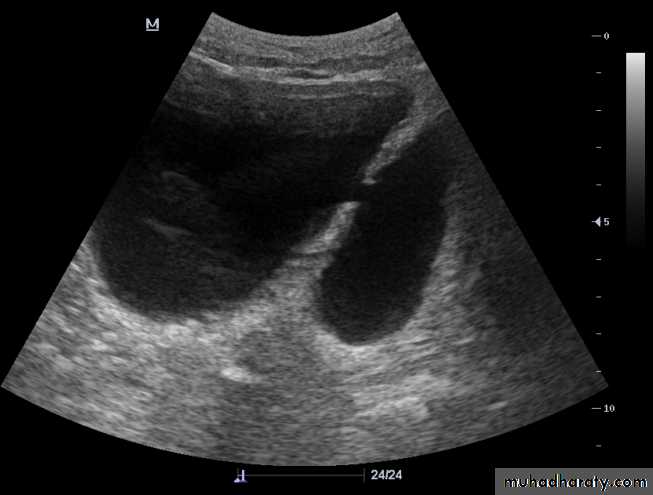

Urinary tract obstruction

The principle feature is dilatation of the PCS and ureter.US show hydronephrosis

Classification of hydronephrosis in grade I–IV.

• Hydronephrosis grade I: dilatation of the renal pelvis without dilatation of the calices without signs of parenchymal atrophy. • Hydronephrosis grade II: dilatation of the renal pelvis and calices. No signs of parenchymal atrophy. • Hydronephrosis grade III: Minor signs of organ atrophy present (flat papillae and blunt fornices).• Hydronephrosis grade IV: massive dilatation of the renal pelvis and calices. Significant signs of renal atrophy (thin parenchyma).